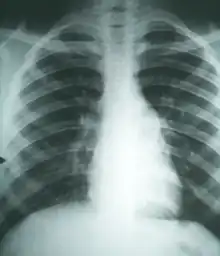

Examen directo de muestras de lesiones Cultivo Biopsia Pruebas inmunológicas Radiografías y tomografía computarizada | |

La infección inicial puede pasar desapercibida o cursar con ligeros síntomas gripales. Las formas progresivas cursan con tos y disnea persistente, debilidad, depresión, fiebre intermitente y pérdida de peso. Después se puede producir osteomielitis con cojeras, abscesos y aborto en hembras gestantes. Agudas o crónicas, las formas progresivas no tratadas son mortales.

- Clínico-epidemiológico: bastante característico, teniendo en cuenta la procedencia o estancia en zonas enzoóticas y el cuadro respiratorio progresivo.

- Lesional: patognomónico a escala microscópica, no es tan característico el macroscópico, que se puede confundir con blastomicosis e histoplasmosis. Histológicamente las lesiones más comunes (34 %) son los granulomas supurativos, sin excluir la presencia de infiltrado linfoplasmocitario, granuloma sarcoidal, inflamación linfoplastrofílica, granuloma necrotizante e inflamación eosinofílica.[1]